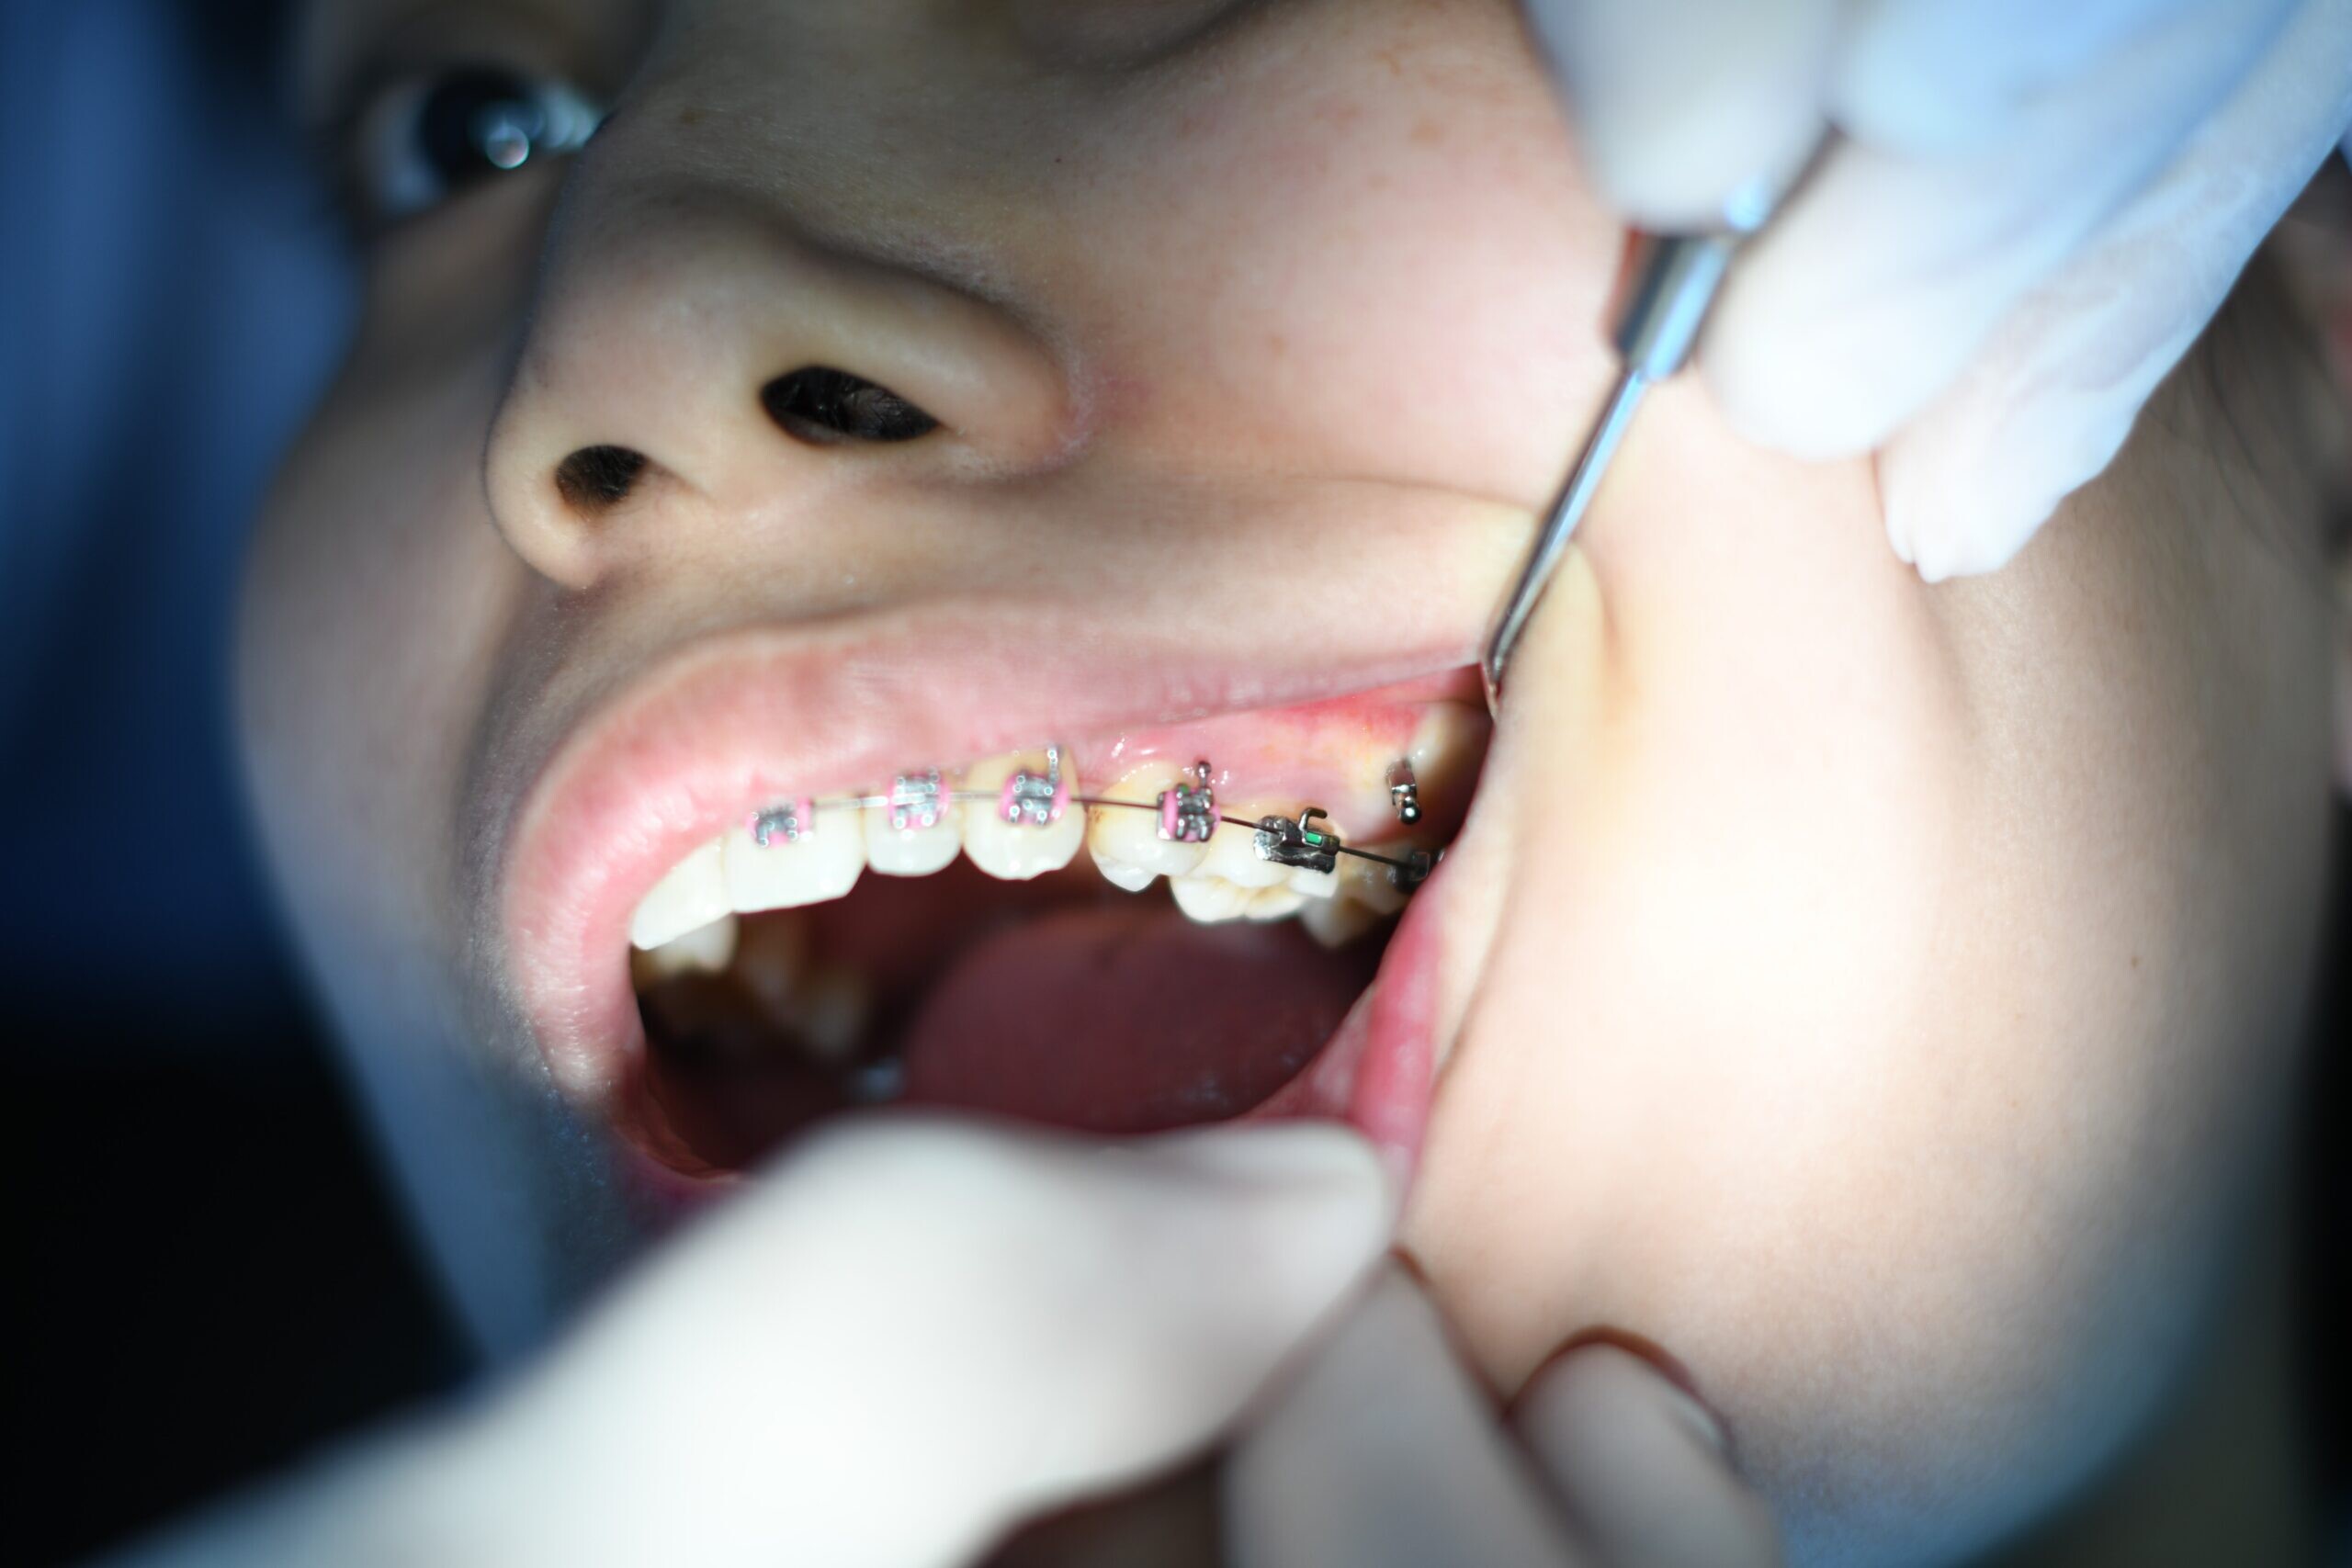

Can I Get Braces if I Have Dental Implants?

Dental implants and braces are both a great option for gaining that healthy, beautiful smile you have always dreamed of. However, these two procedures and treatments don’t go hand in hand. Dental implants act like normal teeth, but in the end, they aren’t natural teeth and that means they can be limited in some aspects, such as getting braces.

What Are Dental Implants?

Dental implants are basically a type of false teeth. They have a metal post that is placed in the bone below the area of a missing tooth. There is then an abutment attached to the post and a false tooth cemented to it. This means that dental implants are fixed in place by metal in your jaw. This is unlike natural teeth that have snaking roots down in your gums rather than attached in such a permanent manner as a dental implant.

What Does This Mean?

This means that a dental implant can’t be moved or adjusted like natural teeth once it’s in place. If attempted, this could result in major damage to the jaw, surrounding teeth, and to the dental implant itself. If orthodontic treatment is desired or needed, this must be completed before the dental implants are placed. Since dental implants are adjusted to fit into the teeth around them, they don’t need special treatments to be straightened. If the surrounding teeth are already straightened or corrected, the dental implants will fit nicely into place with the natural teeth.

Both dental implants and braces are amazing tools for giving you that gorgeous smile you’ve always wanted. However, if you plan on using both, you will have to wait on the dental implants until you’ve completed a round of braces. This may mean having missing teeth until the treatment is complete. Never be afraid to ask your dental professional about the process and what it means for you. Often times, if you have reservations, they have ways to calm those worries. In the end, they’ll ensure you have a smile you can be proud of.